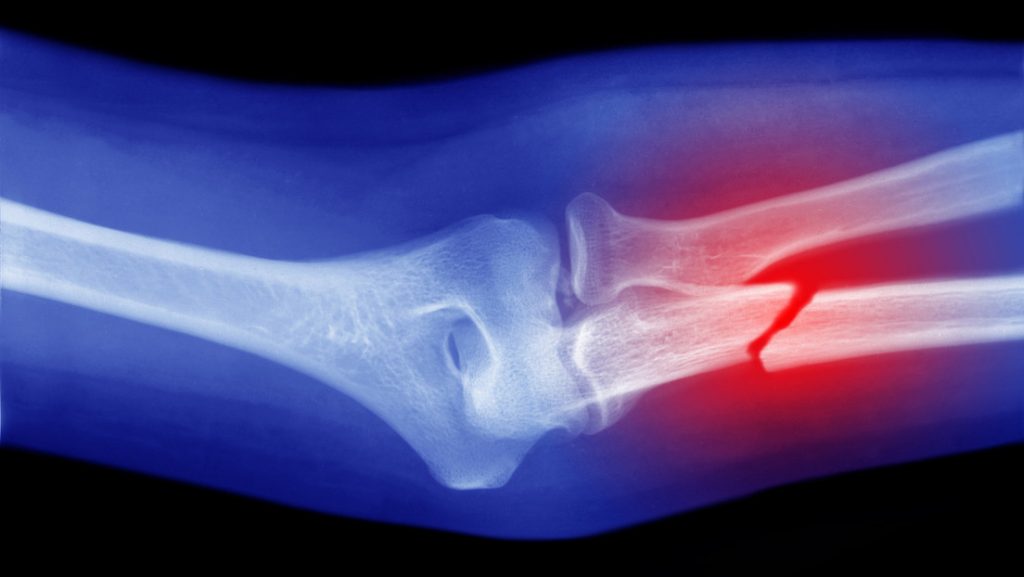

Científicos de la Facultad de Medicina Perelman de la Universidad de Pensilvania (EE.UU.), liderados por el doctor Ling Qin, descubrieron en ratones que un tipo de células madre musculares llamadas Prg4+ pueden transformarse en células óseas y ayudar a reparar fracturas complicadas.

El estudio, publicado en PNAS, reveló que estas células migran al área de la lesión y regeneran el hueso dañado, lo que abre la posibilidad de nuevos tratamientos para fracturas graves en accidentes, lesiones de combate o en adultos mayores con baja masa muscular.